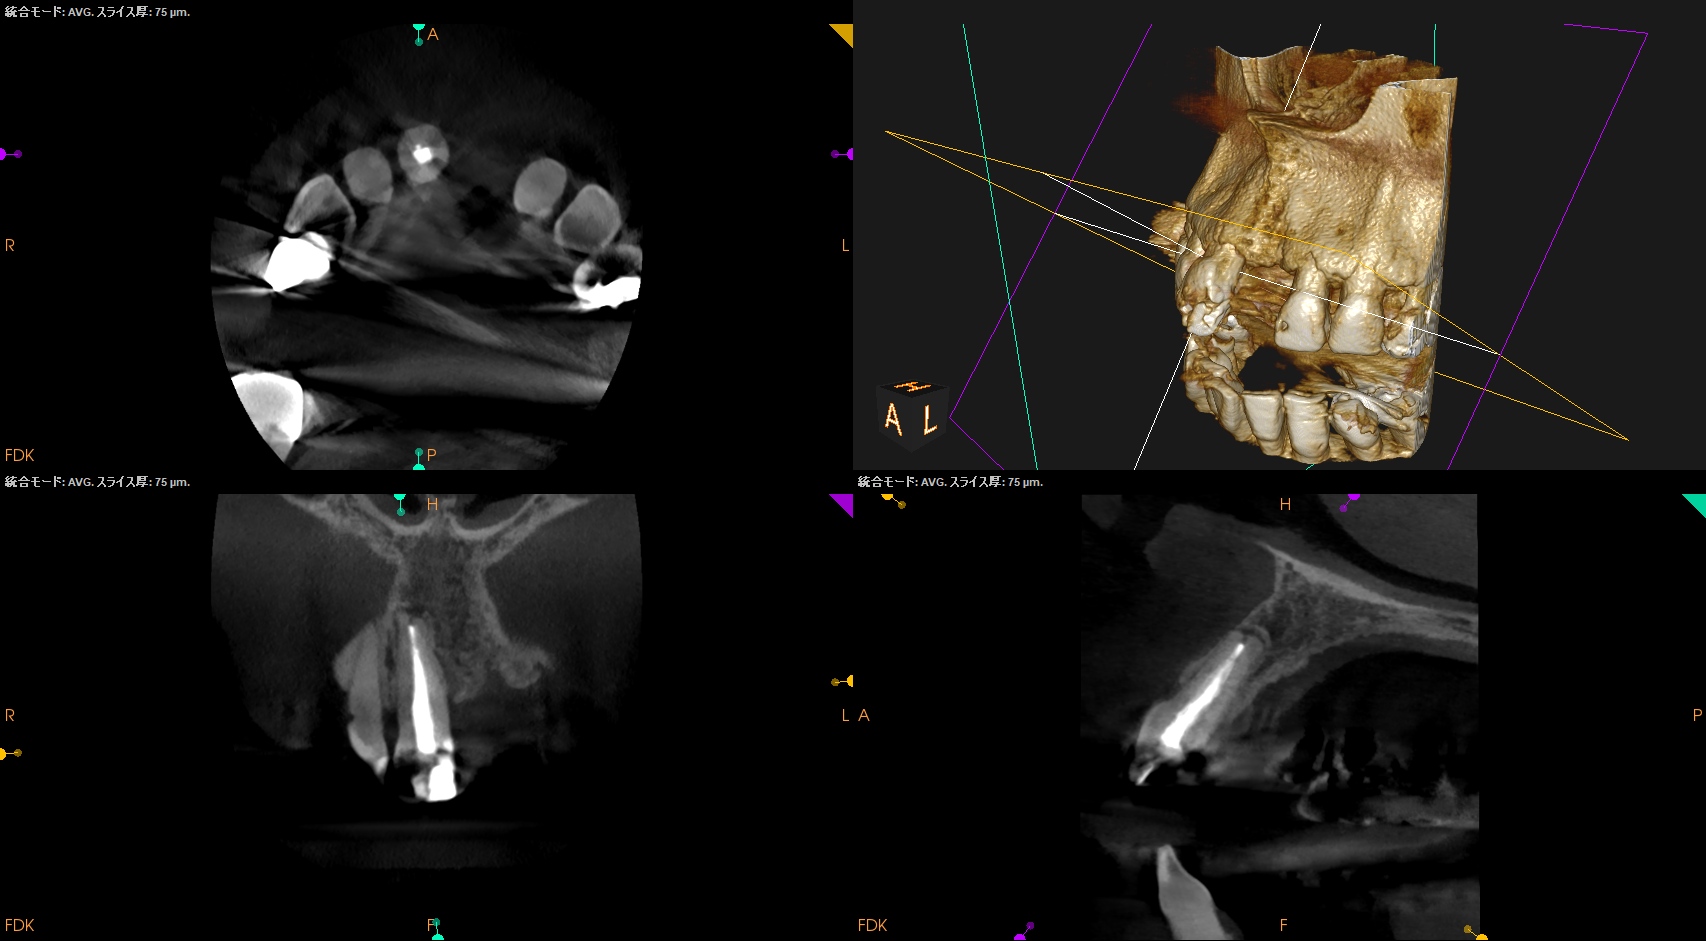

CBCT(2025.10.22)

この部分を攻略できれば勝機がある可能性が90%あるだろう。

攻略できなければ60%だ。